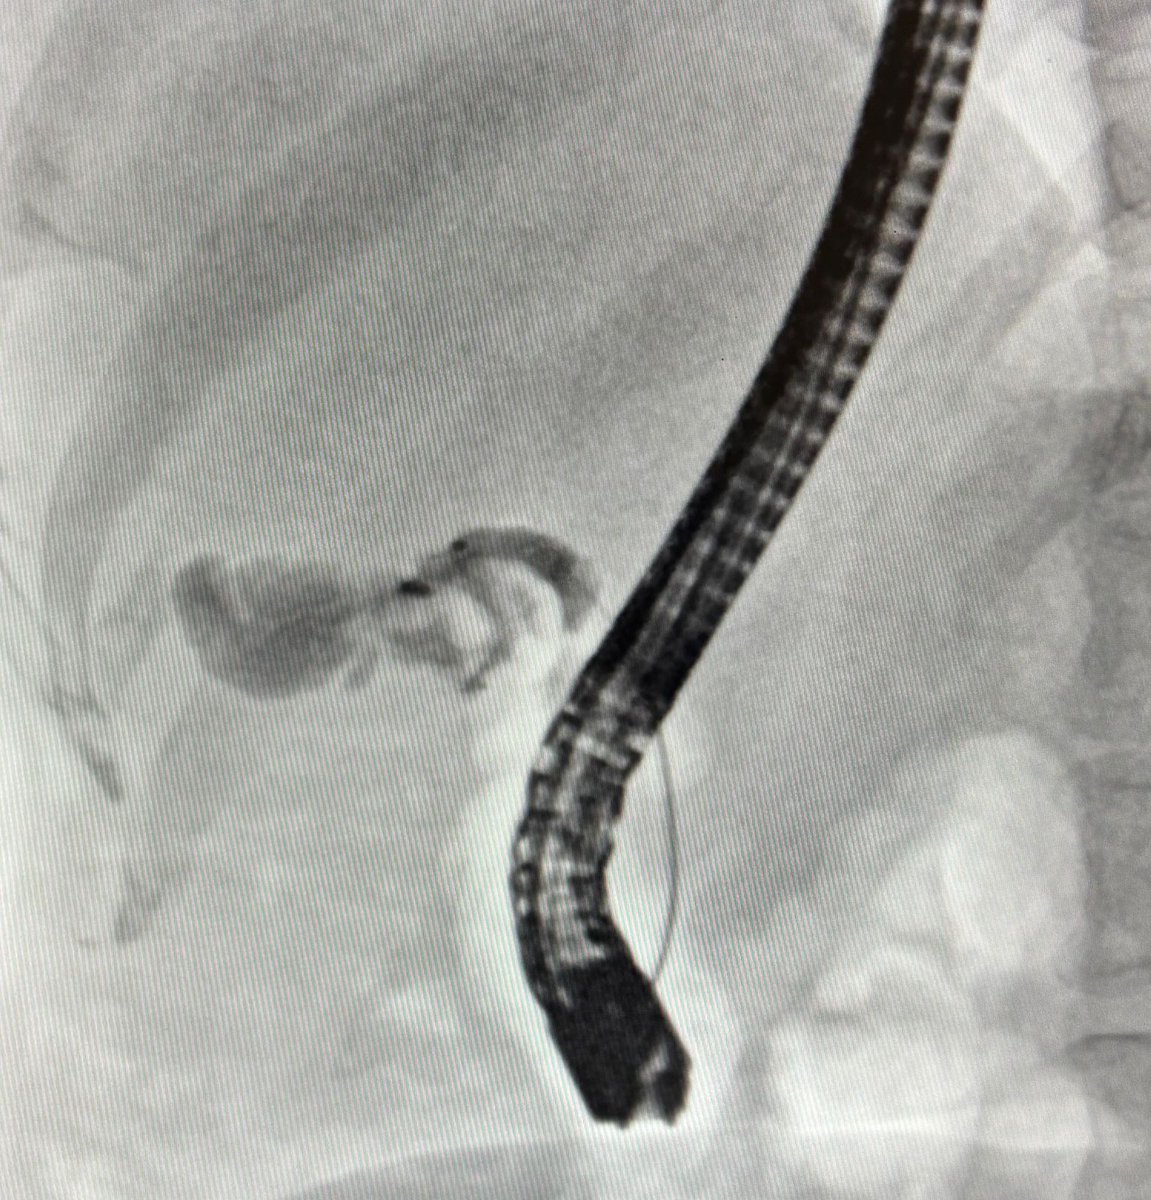

Here's an update on how to deal with a tight Distal PD stricture! A 7Fr Soehendra Stent Retriever was used over the wire to traverse the narrowing

Importance of an adequate initial pancreatogramđź“·Tight Distal Stricture with upstream dilatation identified on occlusion pancreatogram